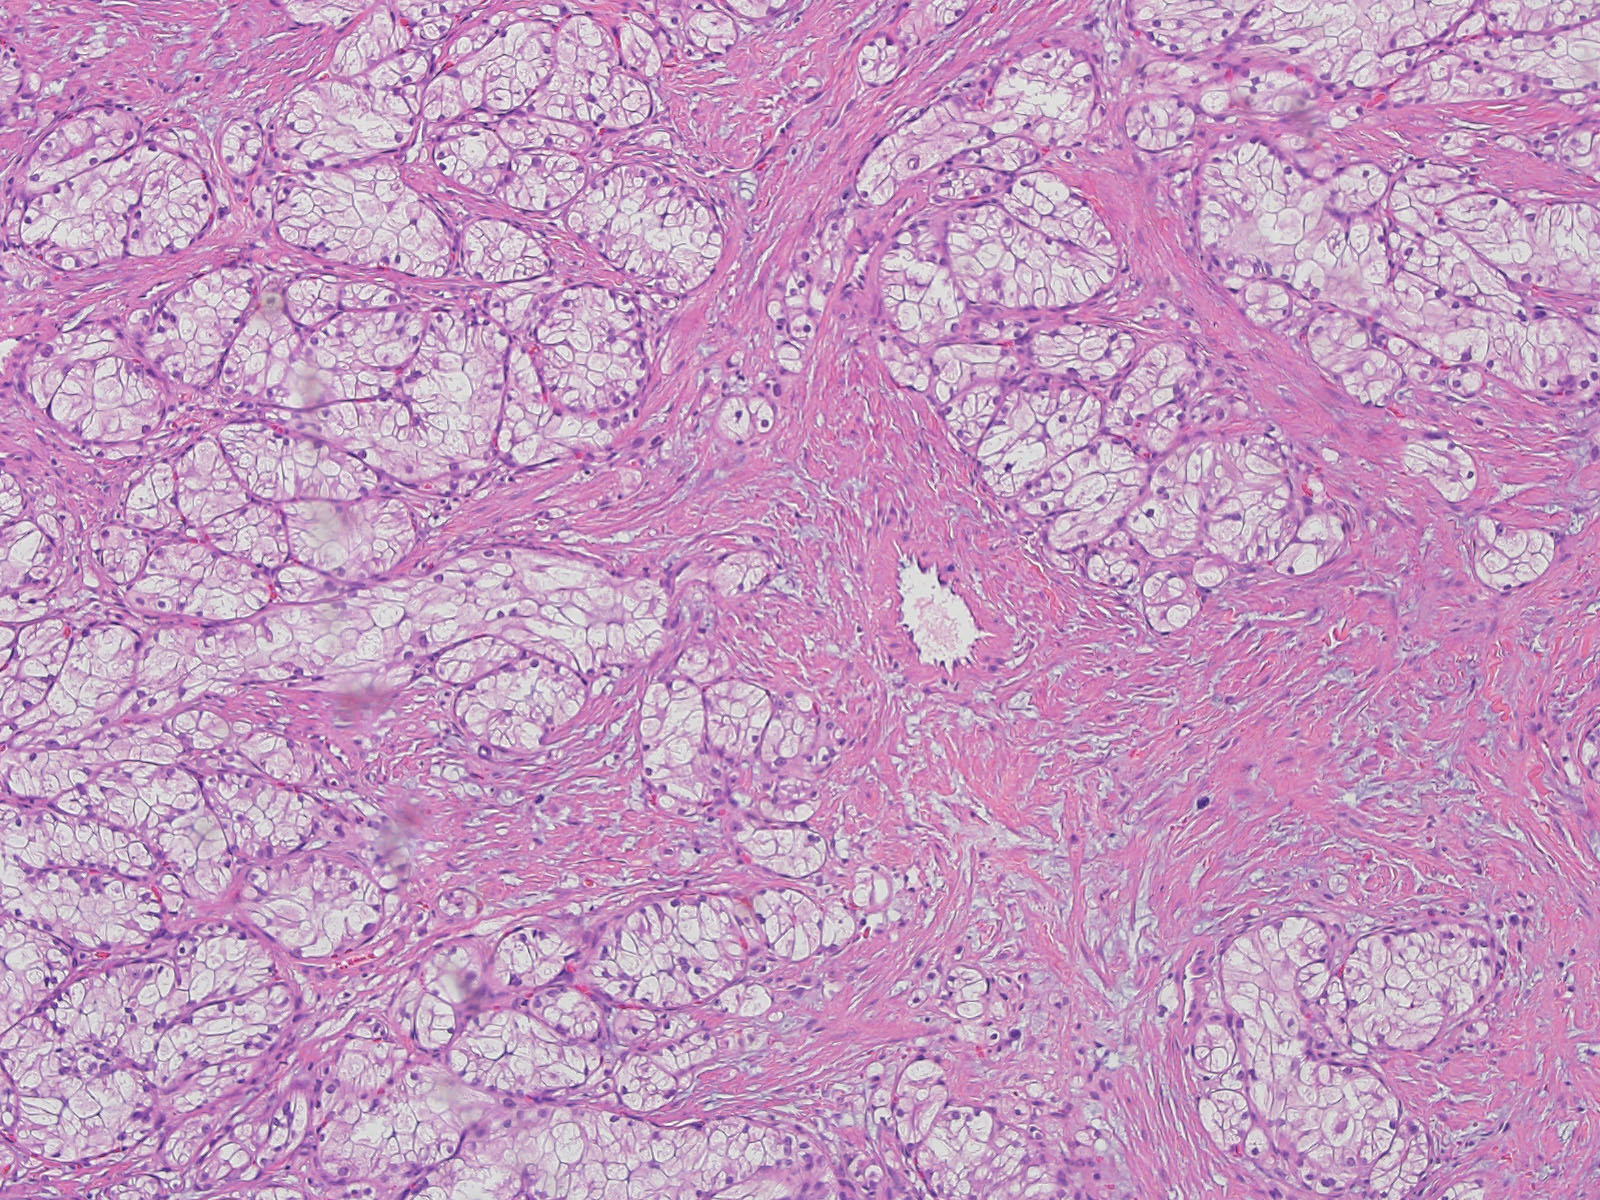

Classification of renal tumors

Case ID: 778